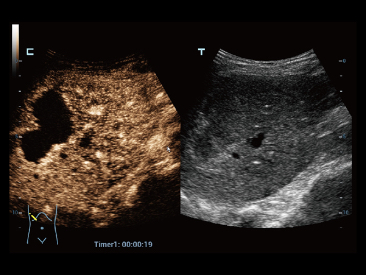

Since the company was founded, Mindray has been continuously exploring new ways to improve diagnostic confidence. Powered by the most revolutionary ZONE Sonography? Technology, Resona 7ŌĆÖs new ZST+ platform brings ultrasound image quality to a higher level by zone acquisition and channel data processing.

As well as the premium level image quality, Resona 7 also enhances clinical research capabilities with the revolutionary V Flow for vascular hemodynamic evaluation, and the most intelligent plane acquisition from 3D datasets for fetal CNS diagnosis. Combining the most intuitive gesture-based multi-touch operation and all the essential clinical features, Resona 7 is truly leading new waves in ultrasound innovation.